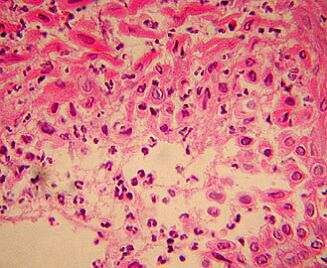

Vesícula con células epiteliales con degeneración hidrópica e infiltrado inflamatorio abundante formado por neutrófilos y macrófagos, coincidente con una infección bacteriana secundaria. H-E x 400.